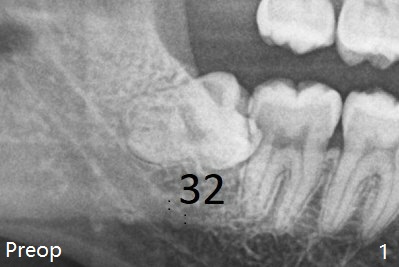

There is bone regeneration 1 year postop (Fig.15,16).